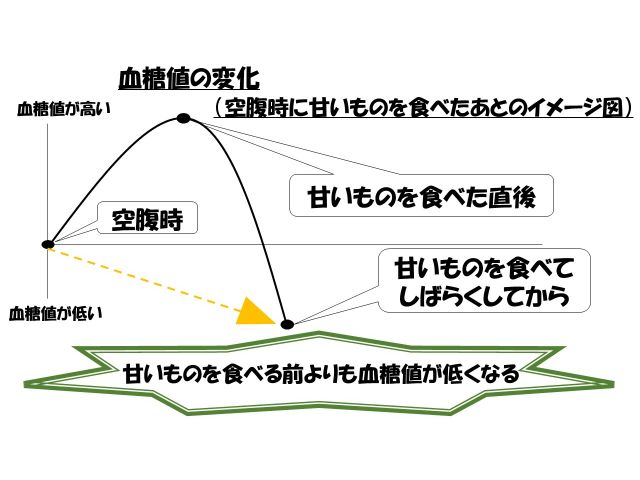

2. 栄養の過不足やタバコなどの物質的な問題

私の経験上では砂糖の影響を受けている人が多いと感じます。

これは血糖値の問題が起きやすくなるでしょう。

血糖値とは

上がるとやる気を感じやすく

下がるとだるさを感じたり、めまいなどを起こしたりするがあります。

例えば空腹時に甘いデザートを食べたとします。

すると血糖値は急激に上昇。

このときはやる気もみなぎり、一見良い状態に見えます。

しかし血糖値は急激に上がると

体は「血糖値を下げなければ!!」と反応。

すると一気に血糖値を下げようとします。

このときインシュリンというホルモンがドバっと分泌。

すると血糖値が急激に下がるのですね。

しかし、空腹時に甘いデザートを食べたことで

血糖値が急上昇

⇩

急降下

その結果、デザートを食べる前よりも血糖値が下がってしまうのです。

(下図参照)